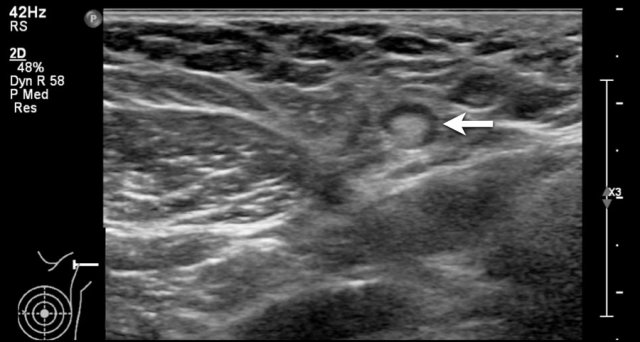

This image is of a patient who presented with a retracted nipple.

There is an irregular tumor behind the nipple with ingrowth into the nipple (arrow).